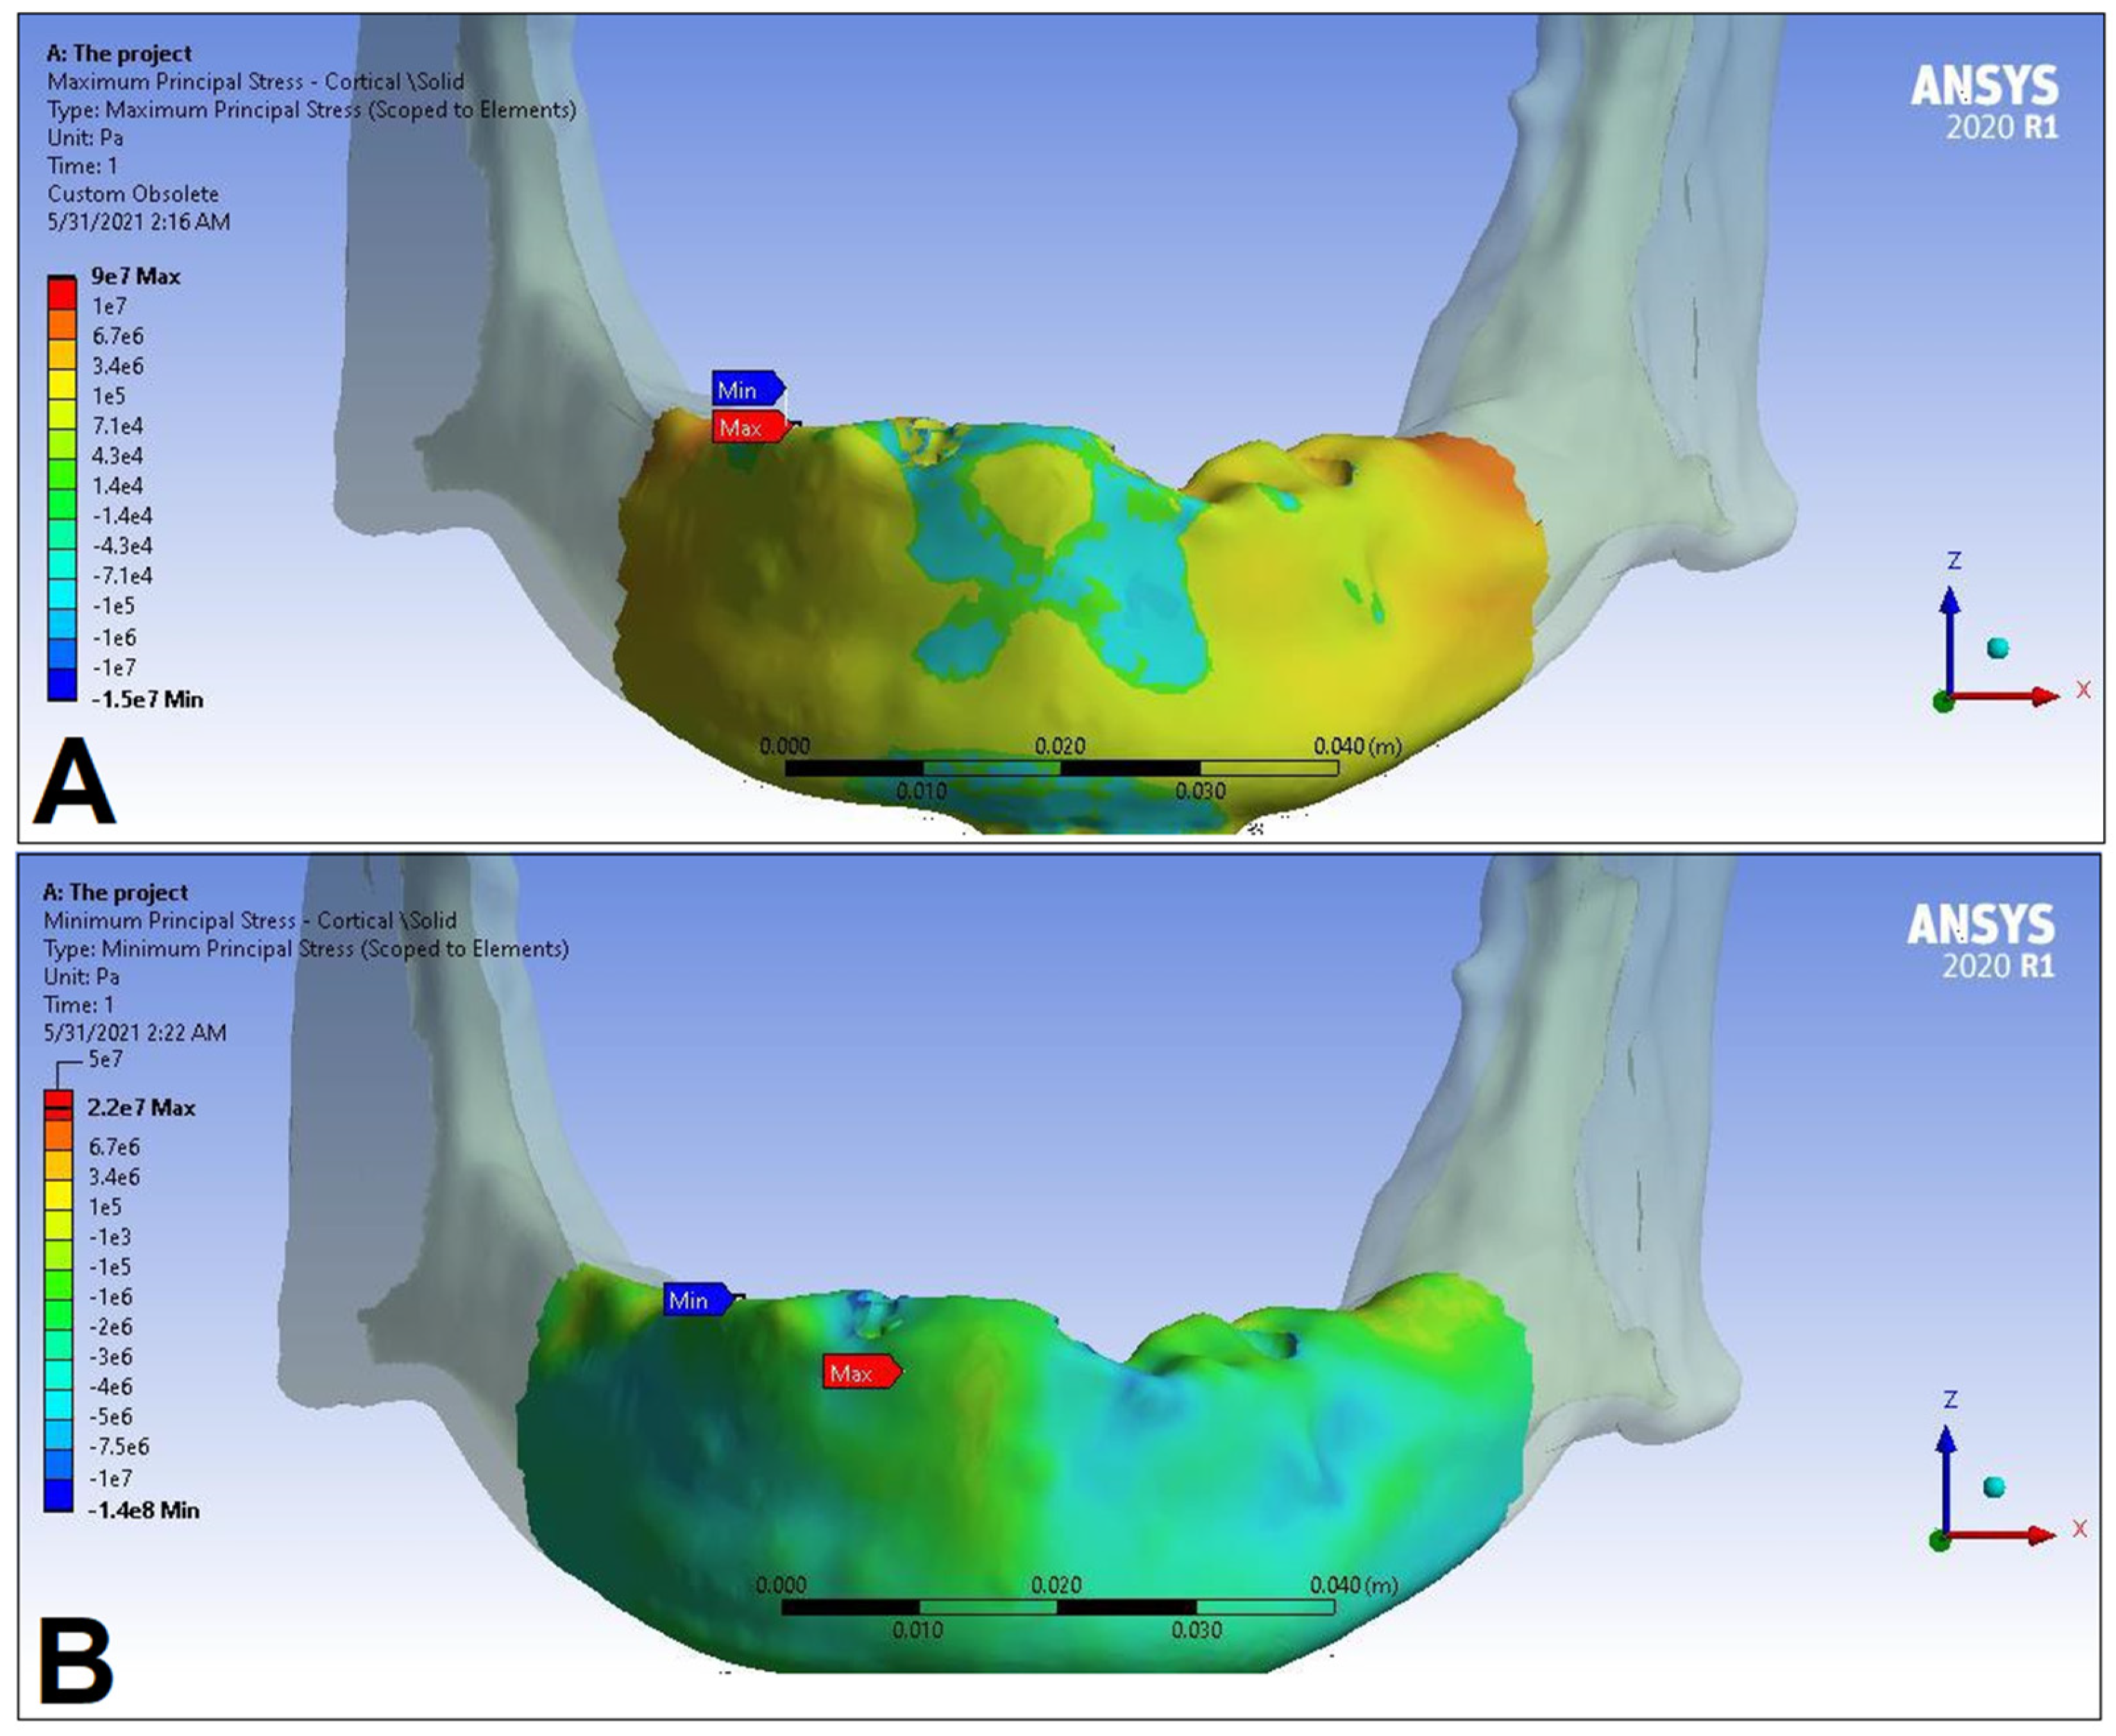

3. Results

| LC1 | LC2 | LC3 | LC4 | ||||||

|---|---|---|---|---|---|---|---|---|---|

| S1 | S2 | S1 | S2 | S1 | S2 | S1 | S2 | ||

| Cortical bone | Pmax [MPa] | 76.39 | 88.51 | 89.57 | 102.98 | 85.63 | 95.48 | 81.02 | 93.15 |

| Pmin [MPa] | −115.30 | −222.76 | −136.4 | −265.35 | −172.30 | −252.61 | −125.20 | −235.32 | |

| Trabecular bone | Pmax [MPa] | 2.49 | 2.24 | 3.03 | 2.62 | 2.95 | 2.52 | 2.92 | 2.59 |

| Pmin [MPa] | −2.81 | −2.89 | −3.34 | −3.38 | −3.25 | −3.25 | −3.49 | −3.52 | |

| Peqv [MPa] | 166.40 | 244.92 | 166.36 | 279.69 | 164.36 | 265.58 | 142.27 | 260.77 | |